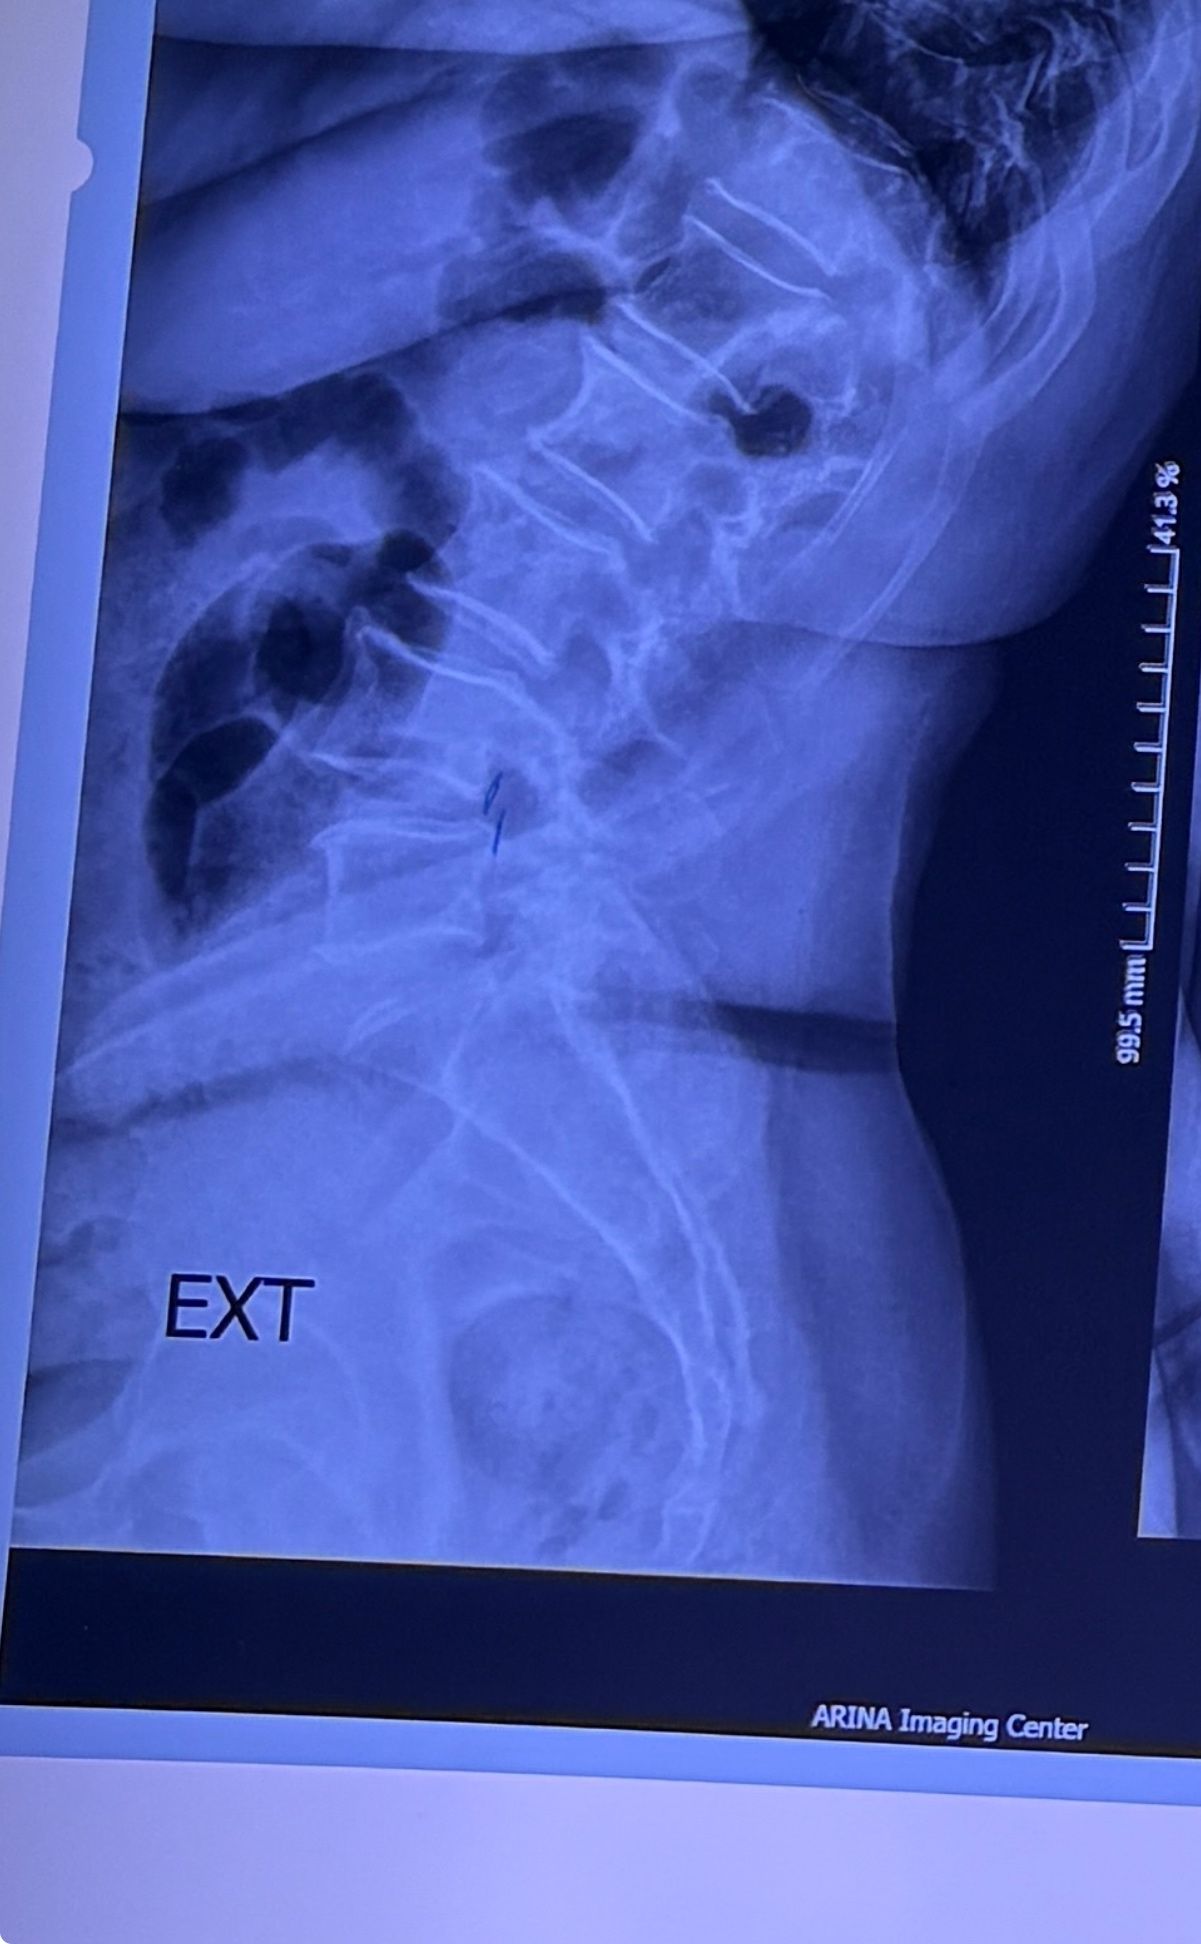

L4-L5 level:

sever L4-5 canal stenosis mainly due to FL hypertrophy?

CSF block. Mild L3 retrolisthesis, facets hypertrophy bilateraly causing L and R IVF stenosis, disc hyperbule

Since I’ve noticed instability in some segments I asked for dynamic L/S x ray:we see mild L4 ant listens due to DjD/DDD. There is not any pars defect.

I will give her treatment via Cox chiropractic flex dis and axial decompression. I would use DTS decompression

Since there is a few mild to moderate DjDs/ DDs in her lower back I won’t use lumbar adjustment on her